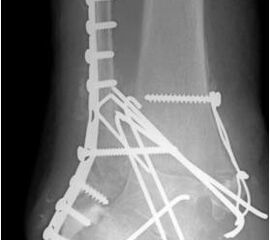

• Primäre oder posttraumatische Arthrose des OSG und USG (Abbildung 1, Abbildung 2).

• Revision einer gescheiterten Fusion des OSG/ USG (Abbildung 3, Abbildung 4).